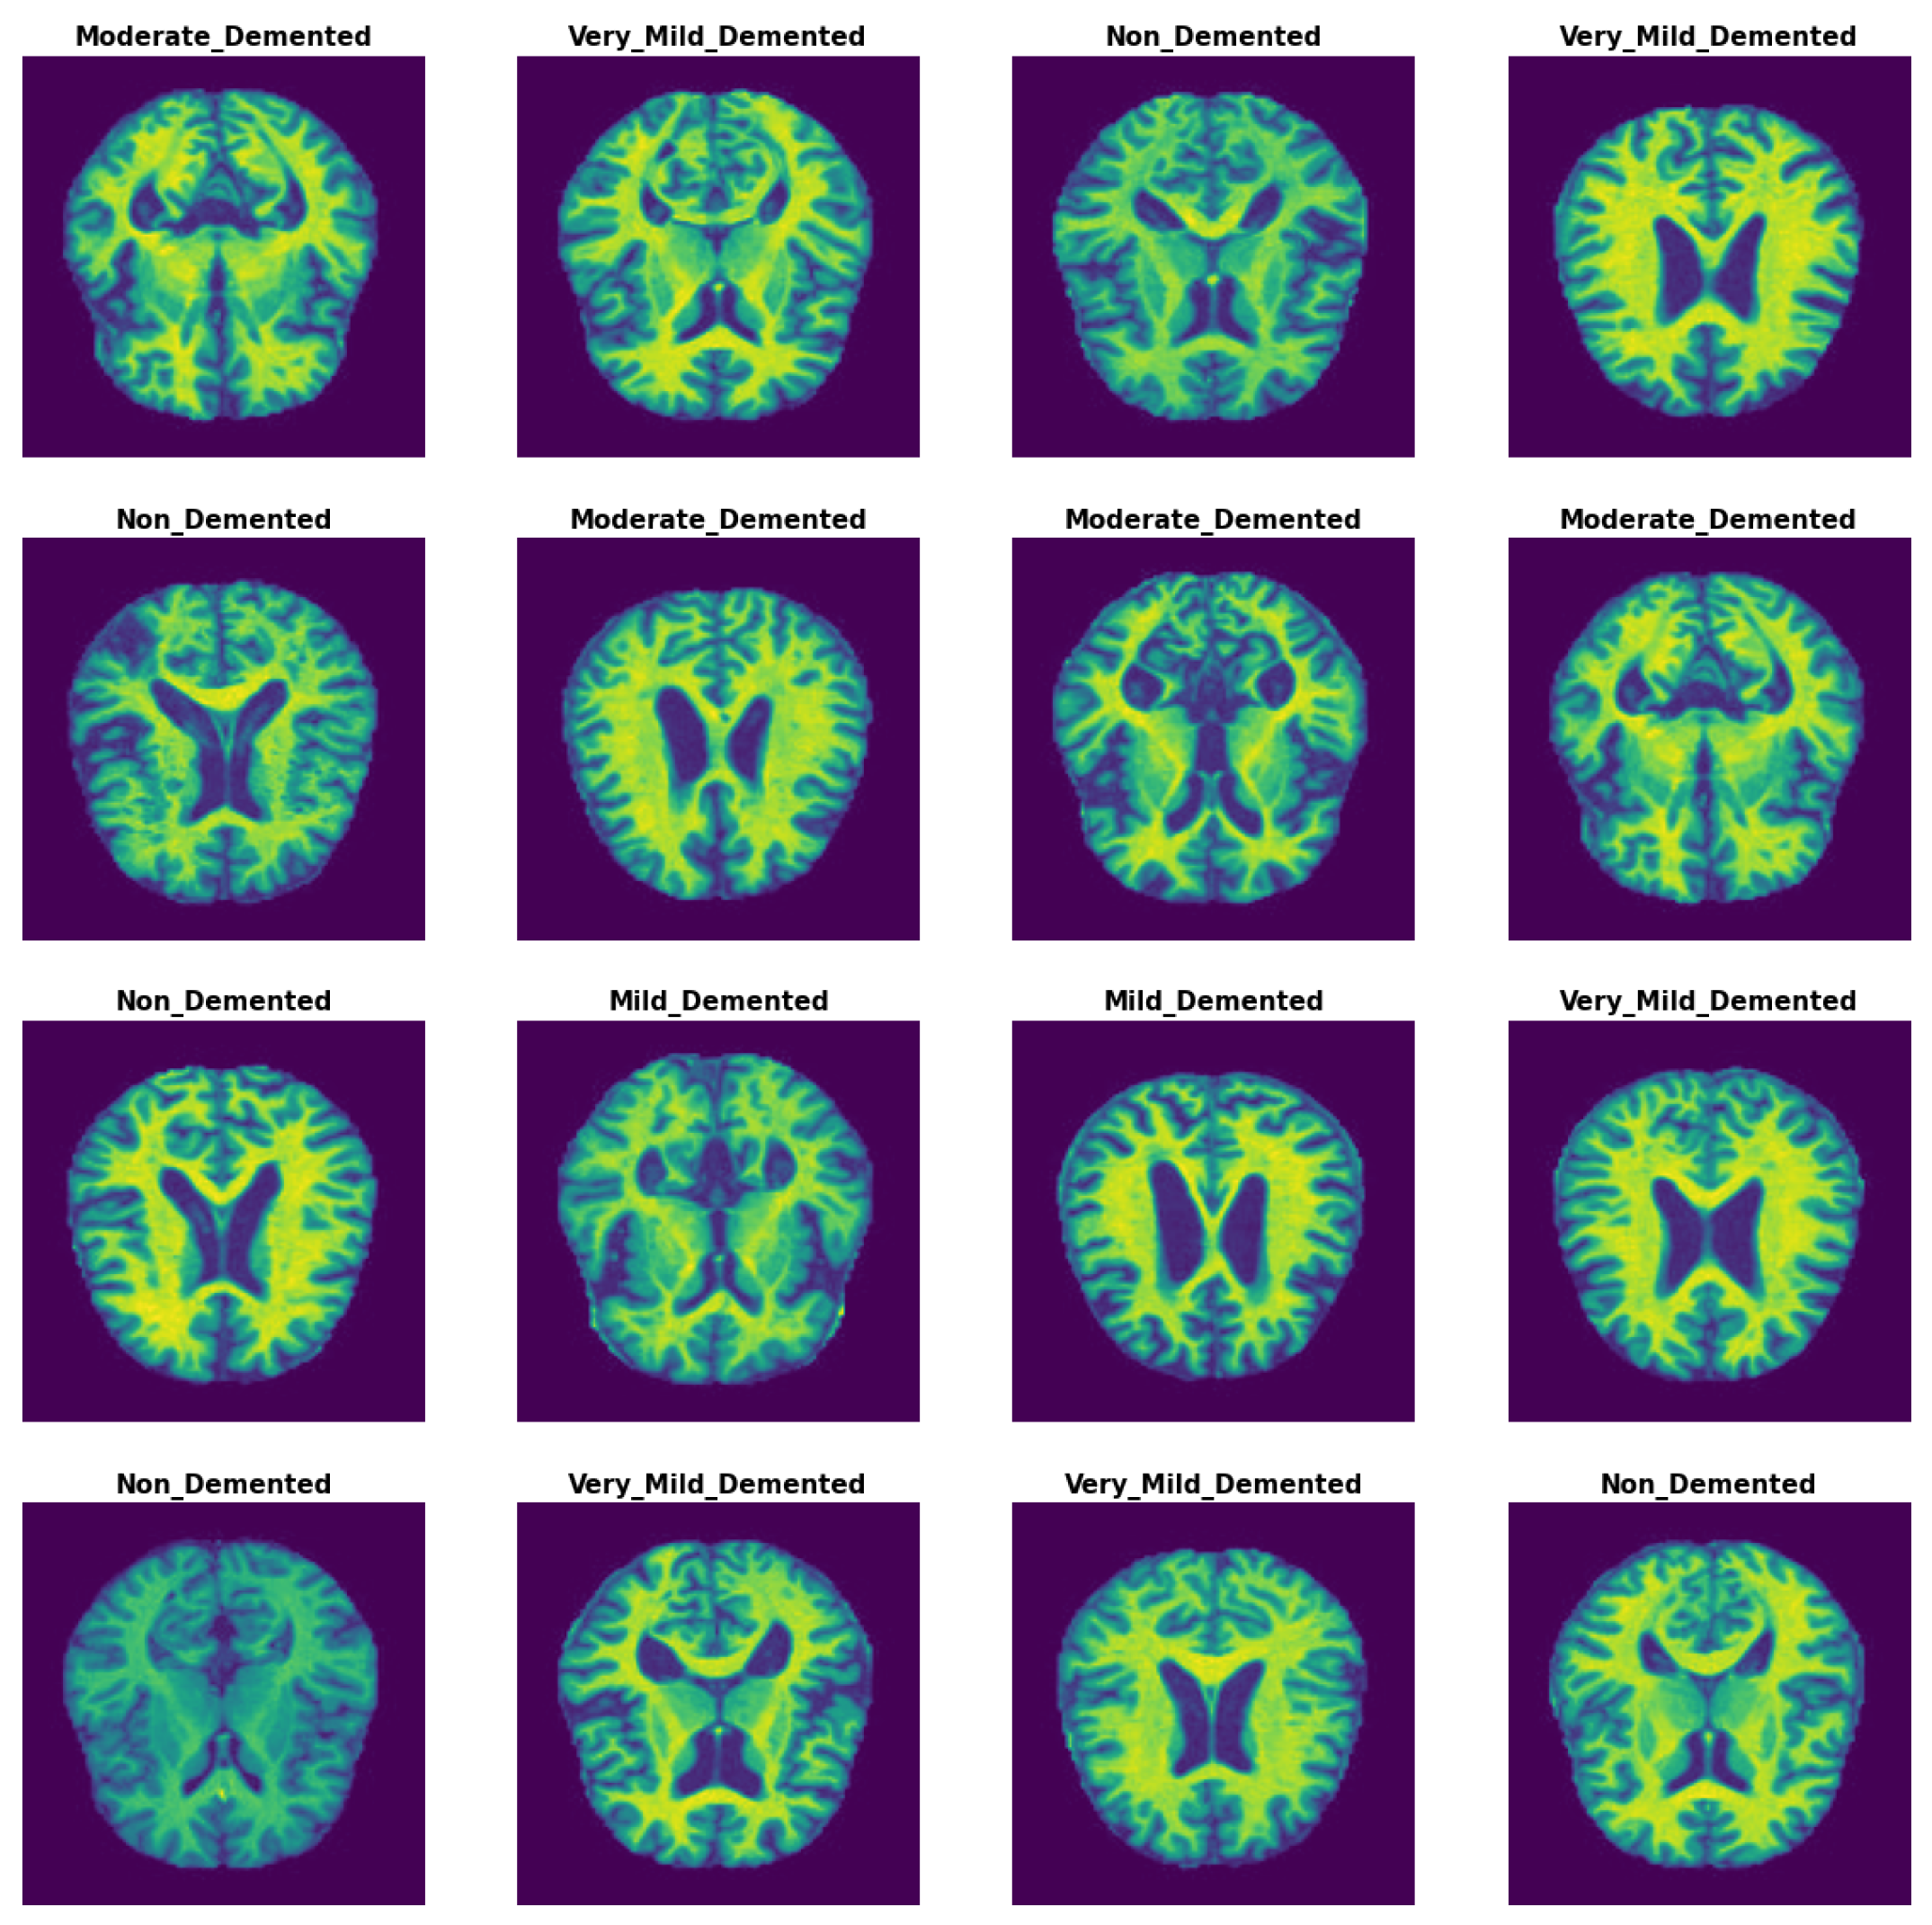

Methods with enhanced capabilities for the detection of AD were established in this study by analyzing MRI images from the AD dataset. The dataset was gathered and downloaded from kaggle [23]. It contained four classes and 6400 images. The 6400 images in the OASIS-2 collection have a size of 176 × 208. The images for each class are shown in Figure 2, with the labels and classes verified. The Alzheimer’s dataset contains the following images for each class: 896 MRIs for mild dementia, 64 MRIs for moderate dementia, 3200 MRIs for non-dementia, and 2240 MRIs for very mild dementia. The samples from the Alzheimer’s dataset are shown in Figure 2.

Figure 2.

MRI image samples from AD dataset.